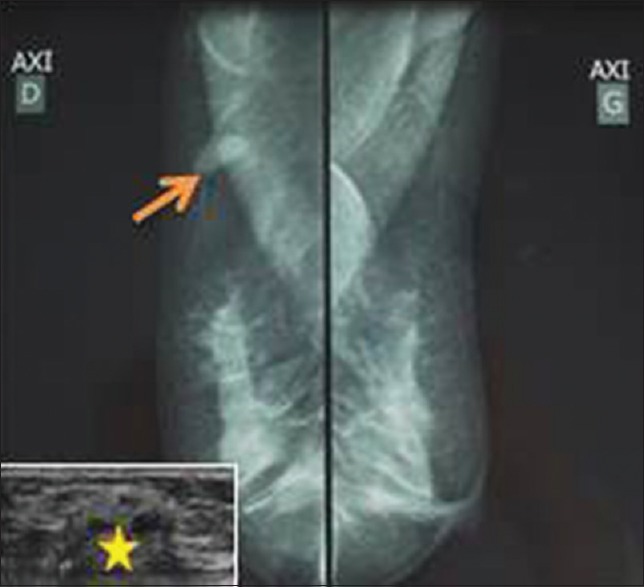

A 43-year-old female, known carrying a right breast nodule diagnosed radiologically and ultrasonographically 1 year ago, underwent evaluation for persistence of the lump. The former mammography and ultrasonography have revealed a well-circumscribed, hyperdense, hyperechogenous solid mass measuring 2 cm × 1 cm × 0.8 cm devoid of micro-calcifications and showing numerous cystic changes suggestive of hamartoma [Figure 1]. Current physical examination revealed a well-defined, nontender, and freely mobile tumor measuring 2 cm in diameter and occupying the upper outer quadrant of the right breast, without any nipple retraction or modification of the overlying skin. Axillary lymph nodes were not palpable. Control ultrasonography showed similar findings as the previous one in addition to the development of a 0.9 cm hyperdense nodule, suggesting an adenofibroma. A surgical excision biopsy of the 2 cm mass was performed.

| Figure 1:Mammographic findings: A well-circumscribed hyperdense solid mass (arrow) measuring 2 cm × 1 cm × 0.8 cm devoid of calcifications (ultrasonography in the lower left corner, the mass was hyperechogenous showing numerous cystic changes [star])